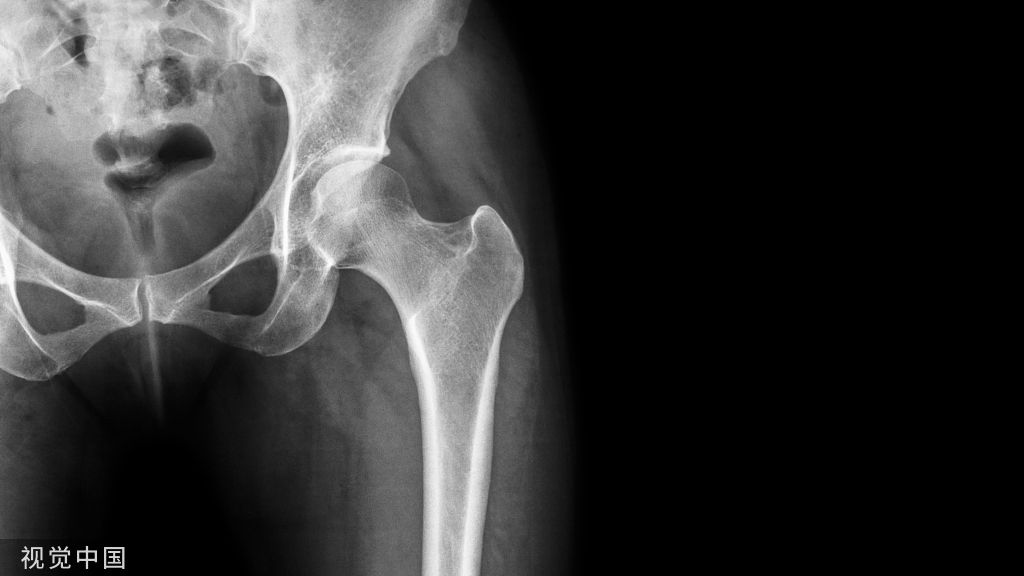

用环形钢丝的张力带固定通常应用在髌骨和尺骨鹰嘴节内骨折,将肌肉牵拉产生的张力转化为骨折面一侧的压力。小的撕脱骨折也可因为张力带固定而受益。钢板也可以采用张力带固定的原理用于固定干骨折,如股骨干骨折。张力带钢丝推荐应用于简单的横形骨折,结合应用拉力螺钉或“O”形钢丝等可以扩大适用范围。